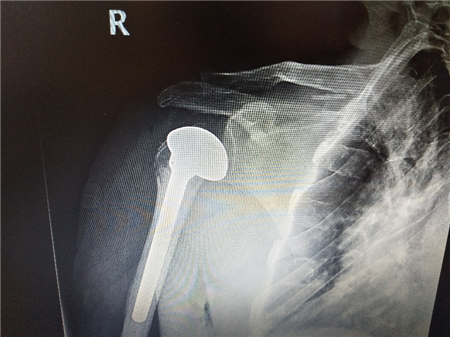

骨外三科团队考虑李大爷年龄较大,并且合并有高血压、重度骨质疏松、颈动脉斑块等基础疾病,预计术中失血多,手术风险大等特点,多次讨论手术方案,最终拟定为李大爷实行“人工肱骨头置换术”。手术非常成功,术后第一天李先生便可自行活动右肩关节,手术切口愈合良好,假体位置良好,无脱位等现象。

术后影像学检查结果